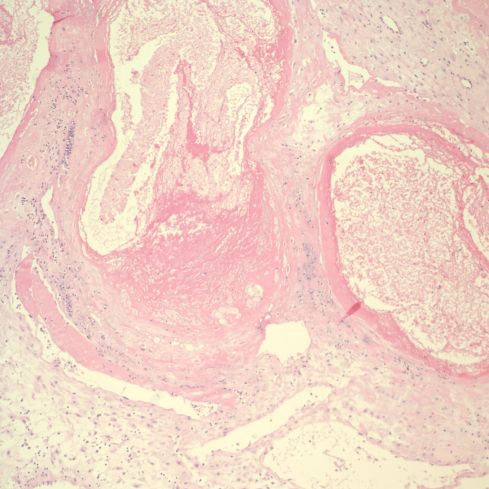

Pathologists see the range of changes described by more systematic research of the trophoblast remodeling of the spiral arteries. The infiltration of the decidua by giant trophoblast cells is often a prominent feature. Plugging of spiral arteries can be seen. Endovascular invasion of spiral arteries may be present (Figs 3,4).

Fig 3: The top portion of decidua demonstrates embedded endometrial glands with plugged mucus in the lumen. Beneath them are two profiles of a remodeled spiral artery. On the left, the arrows point to cytotrophoblast replacing the muscularis. To the right the endothelial lining has been replaced by cytotrophoblast (CT). There are cytotrophoblast, including multinucleated cells surrounding the vessels. At the bottom is the basal cytotrophoblast/fibrinoid layer, and the immature villi can be seen below that band (V). H&E, 10x